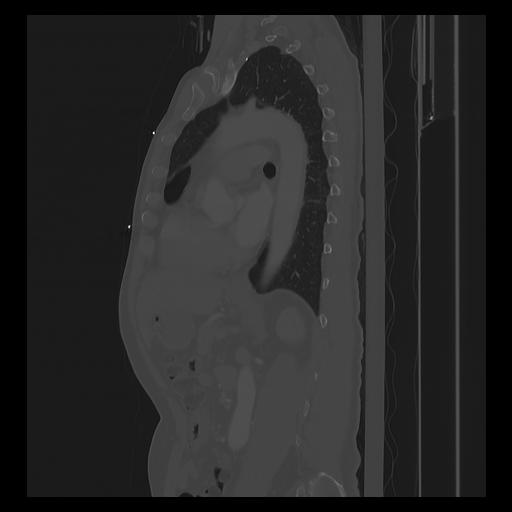

33 PULMON,CE,Sagittal,3.000,PULMON,Sagittal,